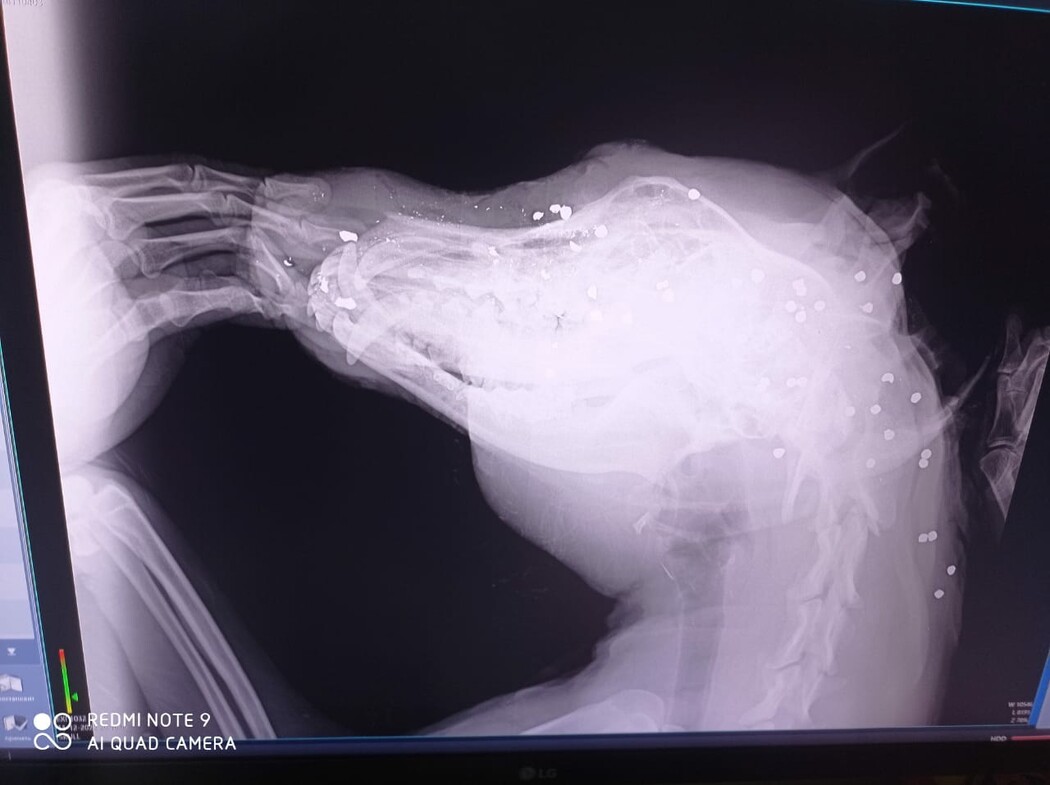

«Сначала было непонятно – то ли огнестрел, то ли ножевое ранение. Начали рану зачищать, и в процессе процедуры нащупали дробь. Сделали рентген, который показал, что у него полголовы забито дробью. Вчера был такой сильный отек у него, что не было понятно, цел ли глаз. Сегодня ездила на обработку и там сказали, что глаз, к сожалению, спасти не удалось. Агору теперь потребуется пластическая операция, потому что само это ранение у него не заживет. В него стреляли практически в упор», – ужасается волонтер.

На фото: снимки Агора